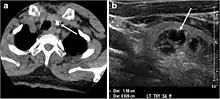

Fig. 7. A 51-year-old female patient post total thyroidectomy for PTC with elevated thyroglobulin measurement. an Axial non-enhanced CT scan of the neck at the level of the thyroid bed demonstrates a well-defined, rounded, homogenously dense soft tissue situated between the trachea and left internal jugular vein (white arrow). b Transverse ultrasound image of the neck demonstrates a well-defined, homogeneous, hypoechoic soft tissue nodule measuring 6 mm (white arrow) with no detected micro-calcifications. Biopsy showed a predominantly residual normal thyroid tissue with micro-foci of PTC.[1] Fig. 7. A 51-year-old female patient post total thyroidectomy for PTC with elevated thyroglobulin measurement. an Axial non-enhanced CT scan of the neck at the level of the thyroid bed demonstrates a well-defined, rounded, homogenously dense soft tissue situated between the trachea and left internal jugular vein (white arrow). b Transverse ultrasound image of the neck demonstrates a well-defined, homogeneous, hypoechoic soft tissue nodule measuring 6 mm (white arrow) with no detected micro-calcifications. Biopsy showed a predominantly residual normal thyroid tissue with micro-foci of PTC.[1]